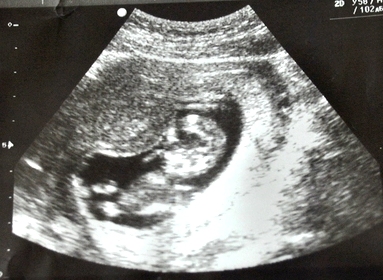

Малыш тихо мирно спал)))) Пока мама вся тряслась)))) Только ручки и ножки поджимал к пузику)))) Само спокойствие и умиротворение) Все говорит в норме, все показала рассказала) Лежал карапуз личиком))) Так что попа и все в той области осталось загадкой))))

Бипариетальный размер 17,8мм - 12 нед и 5 дней

Копчико-теменой размер 58,77мм - 12 нед и 3 дня

Окружность живота 55,87мм - 12 нед и 3 дня

Длина бедренной кости 8,87мм - 12 нед и 4 дня

Длина носовых костей 1,98мм

Сердцебиение 157 ударов в минуту

Хорион по задней стенке

на момент узи 11 недель и 6 дней, по узи 12 недель и 3 дня)